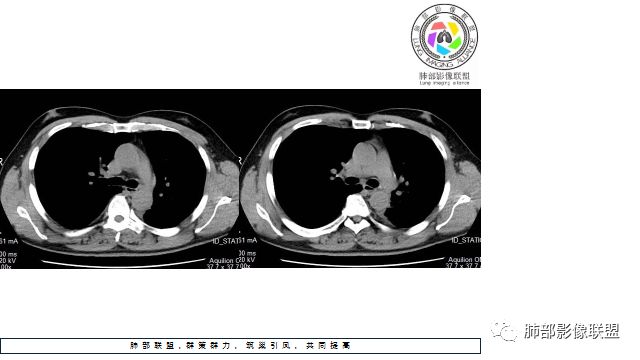

1.左下肺门区巨大肿块,支气管显示不清,轻度阻塞性炎症,没有明显肺不张,提示管腔受压狭窄可能性大于堵塞,这较少见于鳞癌。

2.病灶边缘光滑,未见明显分叶、毛刺,未见明显强化,这符合腺癌影像学特点,却符合神经内分泌癌表现。

3.病灶内密度均匀,轻到中度均匀强化,大病灶未见明显液化坏死区及空洞,不符合鳞癌而符合小细胞肺癌特点。

4.病灶内有肺动脉走形,血管局部受压,未见破坏,病灶乏血供,呈血管包埋或血管造影征;侵袭性力强及破坏力弱、血管漂浮都符合SCLC,所以鳞癌的可能性也不大。

5.左肺门块影或淋巴结肿大,竭力挤兑肺门血管结构,呈冰冻肺门;有时候SCLC可以单独呈现冰冻肺门,而没有没有冰冻纵隔。